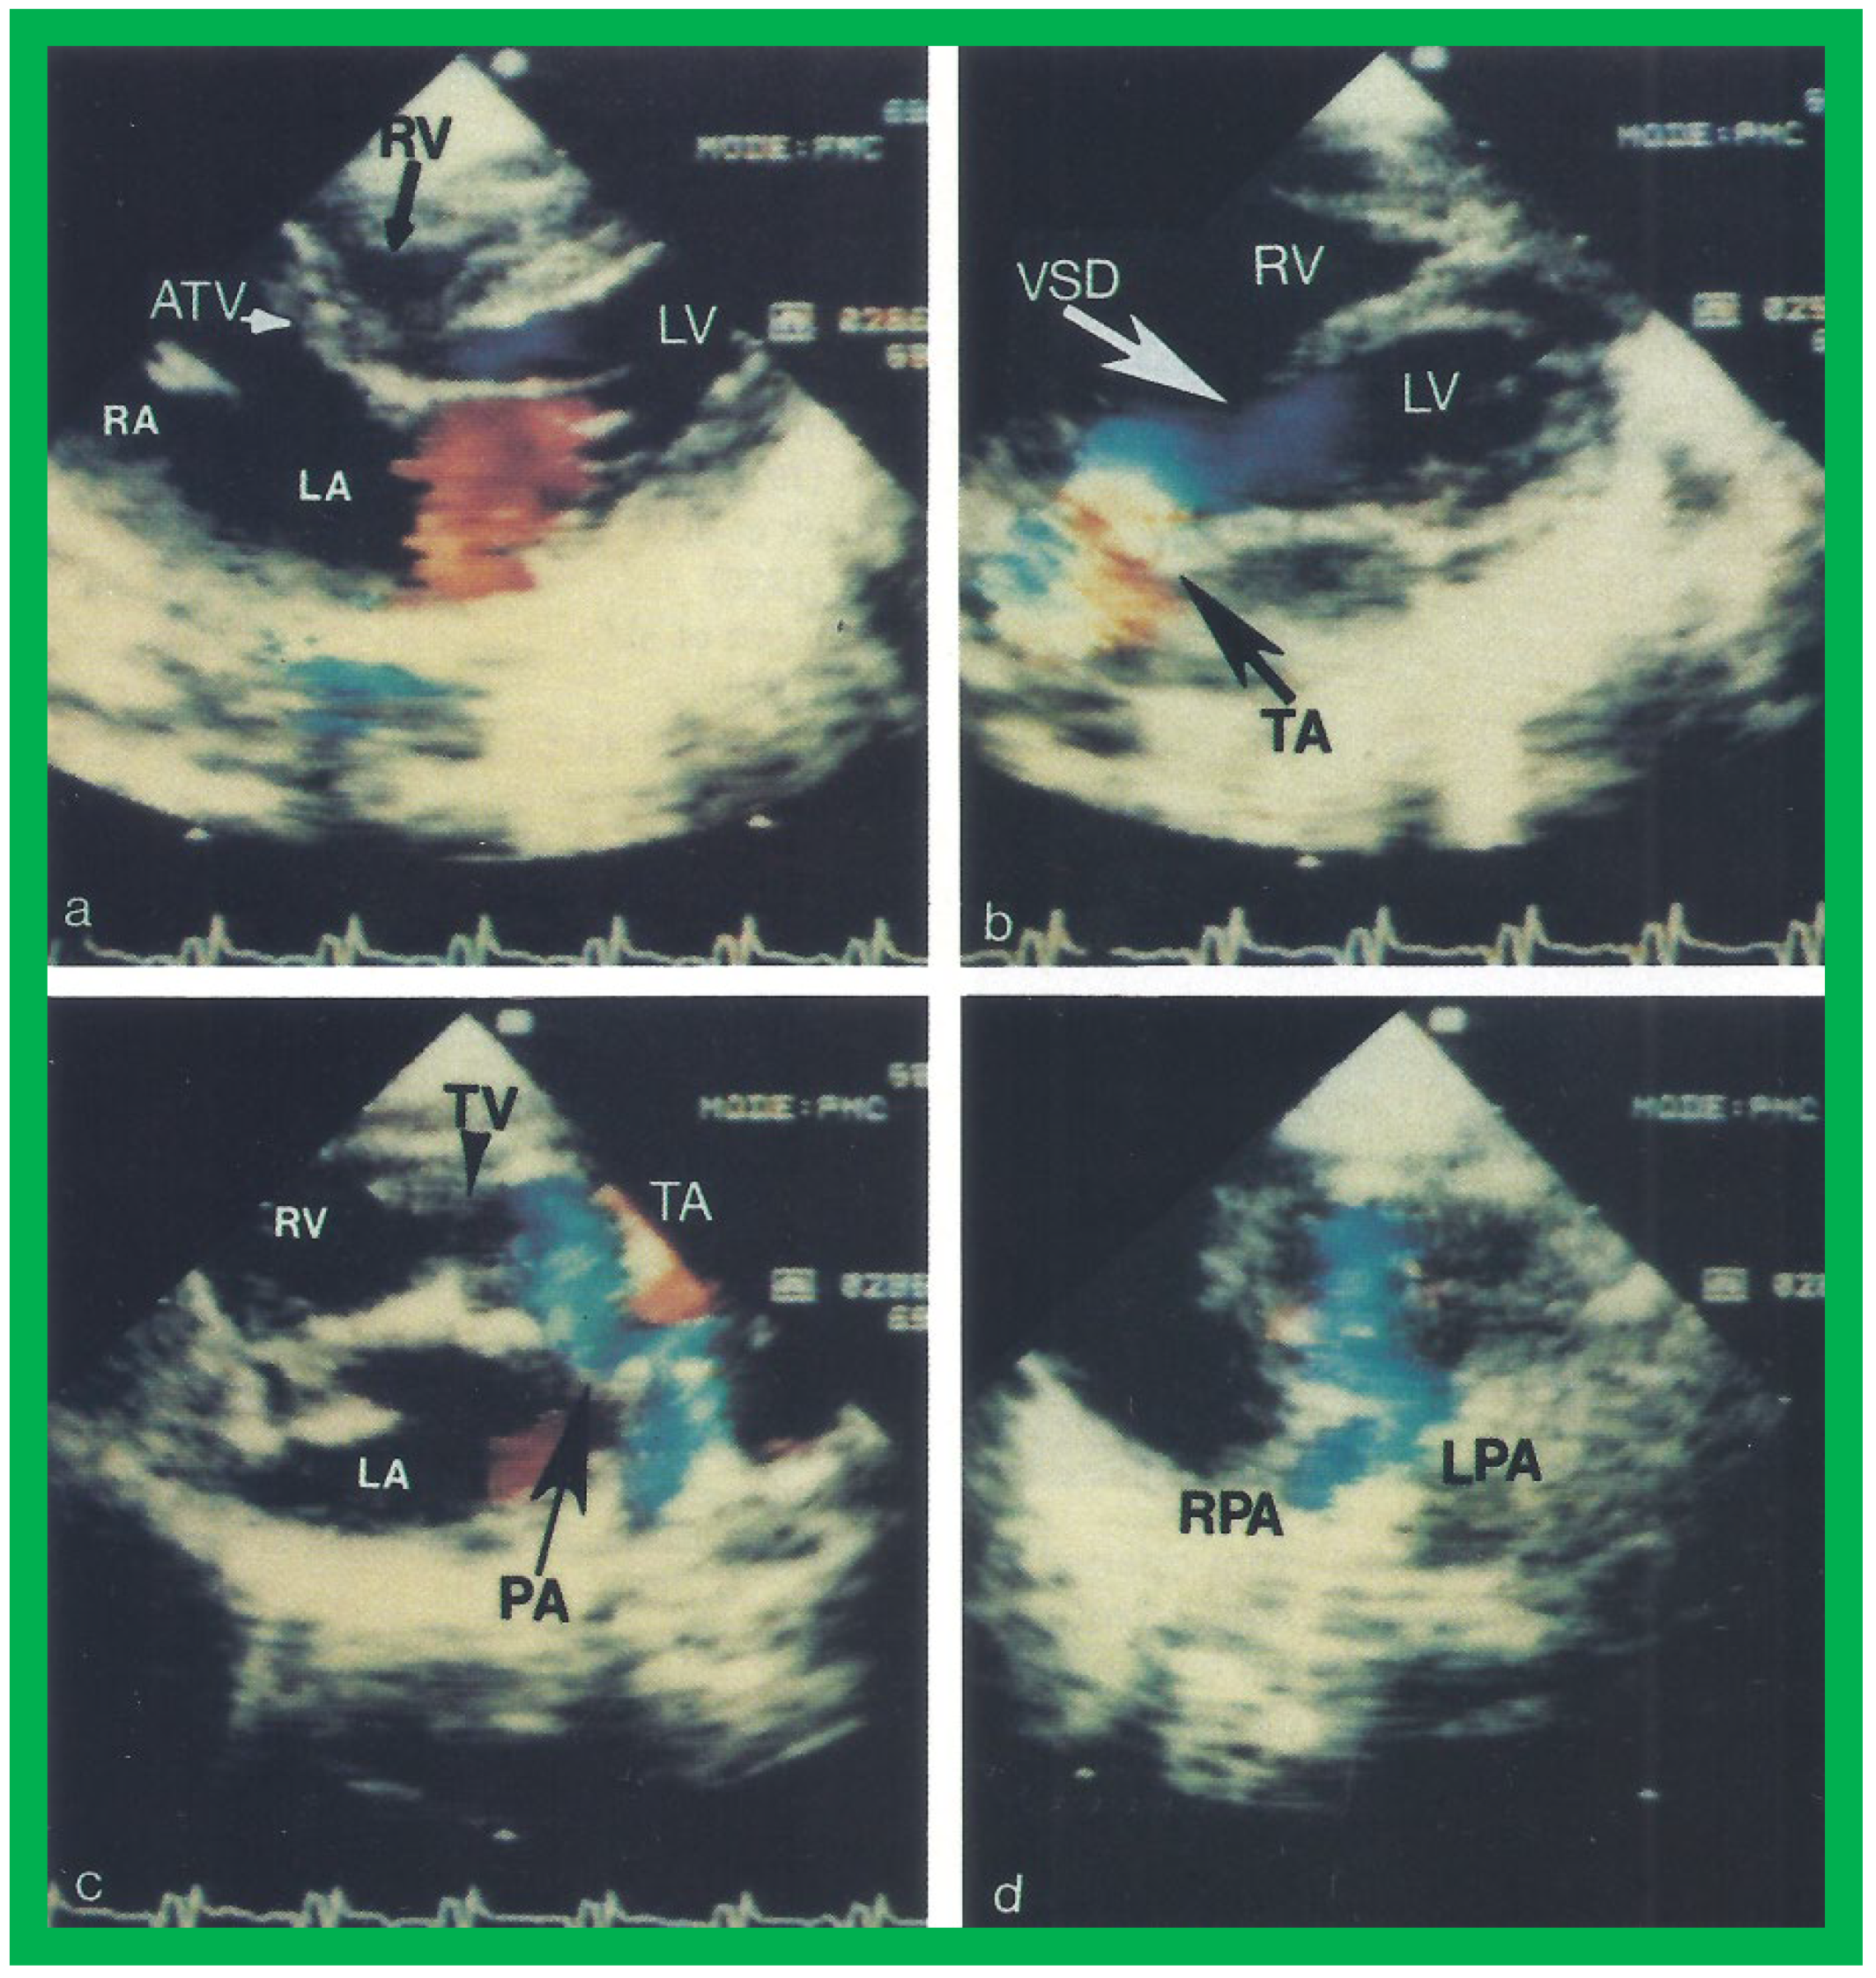

Figure 13. Two dimensional echocardiographic video frames demonstrating (a) an atretic tricuspid valve (ATV) between the right atrium (RA) and right ventricle (RV), (b) a large subtruncal ventricular septal defect (VSD), (c) thickened and somewhat domed truncal valve (TV) leaflets, and (d) the origin of the pulmonary artery (PA) from the posterior aspect of the truncus arteriosus (TA). LA, left atrium; LV, left ventricle. Reproduced from Rao PS, et al. Am Heart J 1991;122:829–835 [31].

The relationship of the great arteries is examined next in order to classify them into various types, as mentioned above. The relationship of the great arteries (Figure 2, top) is established by following the vessels arising from the ventricles until the pulmonary artery (PA) bifurcation or aortic arch. In Type I patients with normally related great arteries, the aorta arises from the LV (Figure 10) and in Type II patients with transposition of the great arteries, the PA arises from the LV (Figure 11; Figure 12). In Type II patients, the blood vessel arising from the LV should be traced to demonstrate its branching into the right and left PAs (Figure 11; Figure 12). In Type III patients, it may be a little more difficult to assign the great artery relationship and, sometimes, other imaging studies, including angiography, may be needed to define the great artery relationship. In Type IV with truncus arteriosus, the limited data suggest that this can be performed by echocardiography (Figure 13; Figure 15). In the example shown [31], the atretic tricuspid valve (Figure 13a and Figure 14a), VSD (Figure 13b and Figure 14b), hypoplastic RV (Figure 14a), single vessel (truncus) arising from the heart (Figure 13c,d, and Figure 14c,d), and origin of the PA and its division into branch PAs (Figure 13d, and Figure 14c,d) were demonstrated.